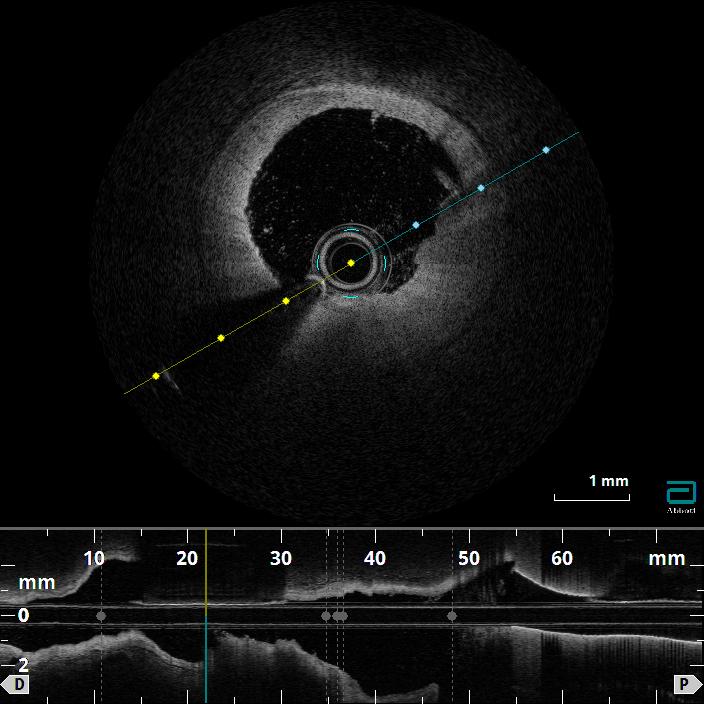

Coronary angiography confirmed a hemodynamically significant stenosis in the mid-LAD, consistent with CCTA. OFDI revealed a high-intensity, heterogeneous signal with layered structure and microchannel formation, features suggestive of an organized thrombus rather than a lipid-rich atherosclerotic plaque. This morphology was considered to be associated with a low risk of plaque restenosis and favorable balloon response, making a stent-free strategy a reasonable therapeutic option.

The target mid-LAD lesion was initially treated with excimer laser coronary angioplasty (ELCA) to ablate thrombotic tissue and facilitate subsequent vessel preparation. Following laser irradiation, prolonged low-pressure balloon dilatation was performed to optimize lesion modification and achieve adequate luminal expansion. Subsequently, a paclitaxel-coated drug-coated balloon (DCB) was applied at the treated segment to deliver antiproliferative therapy without stent implantation. Final angiography showed satisfactory luminal gain with TIMI 3 flow, and no evidence of vessel recoil or major dissection. Post-procedural OFDI confirmed a well-expanded lumen with smooth vessel surface, and no significant residual thrombus or flow-limiting dissection. The patient was discharged on dual antiplatelet therapy for 3 months. At 2-year follow-up, CCTA demonstrated sustained vessel patency without restenosis, supporting the long-term durability of this stentless ELCA+DCB strategy.